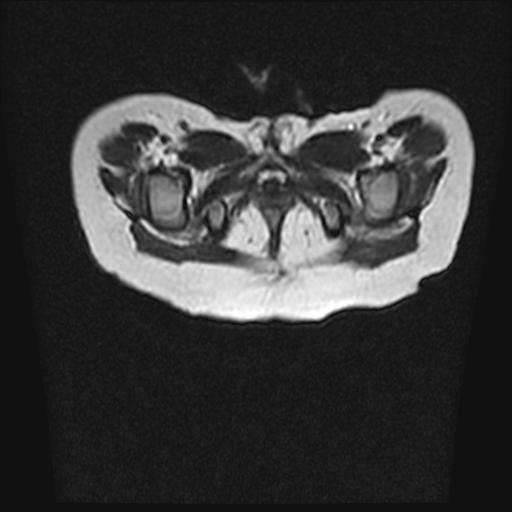

四个月的女婴,ct示脊膜膨出.

脂肪脊髓脊膜膨出

脊柱裂、脊膜膨出